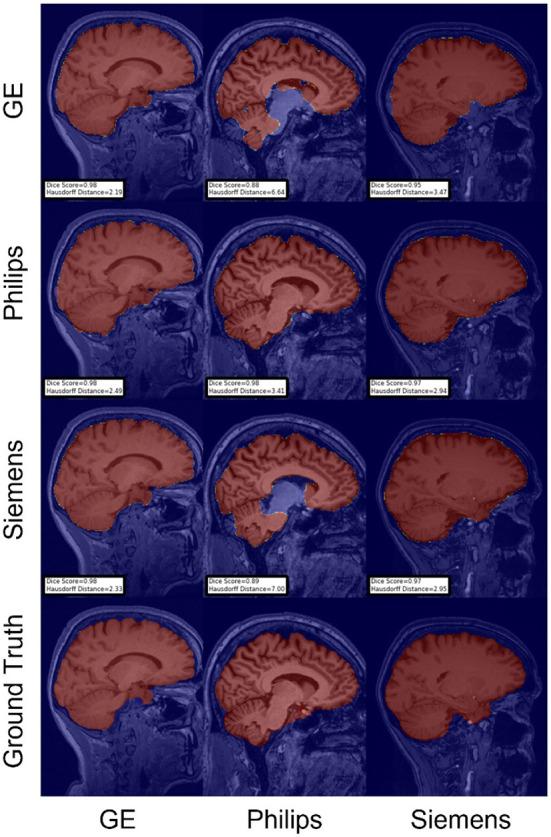

Accurate brain segmentation is critical for magnetic resonance imaging (MRI) analysis pipelines. Machine-learning-based brain MR image segmentation methods are among the state-of-the-art techniques for this task. Nevertheless, the segmentations produced by machine learning models often degrade in the presence of expected domain shifts between the test and train sets data distributions. These domain shifts are expected due to several factors, such as scanner hardware and software differences, technology updates, and differences in MRI acquisition parameters. Domain adaptation (DA) methods can make machine learning models more resilient to these domain shifts. This paper proposes a benchmark for investigating DA techniques for brain MR image segmentation using data collected across sites with scanners from different vendors (Philips, Siemens, and General Electric). Our work provides labeled data, publicly available source code for a set of baseline and DA models, and a benchmark for assessing different brain MR image segmentation techniques. We applied the proposed benchmark to evaluate two segmentation tasks: skull-stripping; and white-matter, gray-matter, and cerebrospinal fluid segmentation, but the benchmark can be extended to other brain structures. Our main findings during the development of this benchmark are that there is not a single DA technique that consistently outperforms others, and hyperparameter tuning and computational times for these methods still pose a challenge before broader adoption of these methods in the clinical practice.

准确的脑部分割对于磁共振成像(MRI)分析流程至关重要。基于机器学习的脑磁共振图像分割方法是完成这项任务的最先进技术之一。然而,在测试集和训练集数据分布之间存在预期的域偏移时,机器学习模型生成的分割结果往往会退化。由于多种因素,如扫描仪硬件和软件差异、技术更新以及MRI采集参数的差异,这些域偏移是预期会出现的。域适应(DA)方法可以使机器学习模型对这些域偏移更具弹性。本文提出了一个基准,用于使用从不同供应商(飞利浦、西门子和通用电气)的扫描仪跨站点收集的数据来研究脑磁共振图像分割的DA技术。我们的工作提供了标记数据、一组基线模型和DA模型的公开可用源代码,以及一个用于评估不同脑磁共振图像分割技术的基准。我们应用所提出的基准来评估两项分割任务:去颅骨;以及白质、灰质和脑脊液分割,但该基准可以扩展到其他脑结构。我们在开发此基准过程中的主要发现是,没有一种DA技术能始终优于其他技术,并且在这些方法更广泛地应用于临床实践之前,这些方法的超参数调整和计算时间仍然是一个挑战。